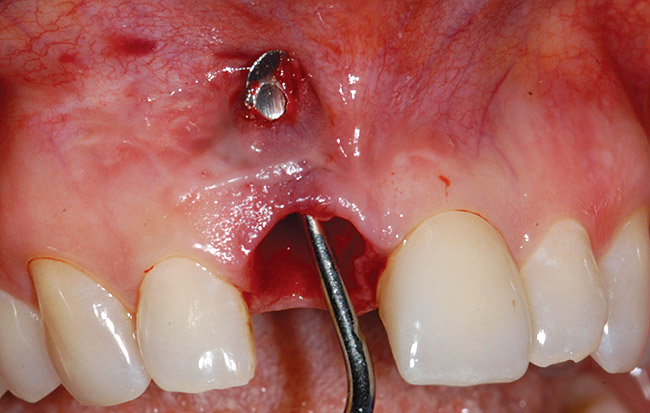

A 39-year-old woman presented with a failing endodontically treated maxillary right central incisor. Clinical and radiographic examination revealed a thick, flat periodontal biotype, high smile line, and a fistulous tract of the labial vestibule opposite the incisor (Figure 16 and Figure 17). Also noted post-extraction was a thin (< 2 mm) labial plate with 8 mm of vertical bone loss (Figure 18). Treatment consisted of a conservative flapless extraction with placement of a free connective tissue graft (Figure 19) sutured through the socket, along with placement of a bone mineralized allograft (MinerOss) (Figure 20 and Figure 21). Five months post-extraction, a root-form implant was placed, nonsubmerged, along with a bovine bone xenograft as a veneer into a sub-periosteal labial pouch (Figure 22 through Figure 24). A provisional crown was placed 3 months later, allowing for adequate soft-tissue grooming (Figure 25).

Figure 18  Post-extraction socket defect with loss of labial plate.

Figure 18

Figure 19  Connective tissue graft introduced via extraction socket.

Figure 19